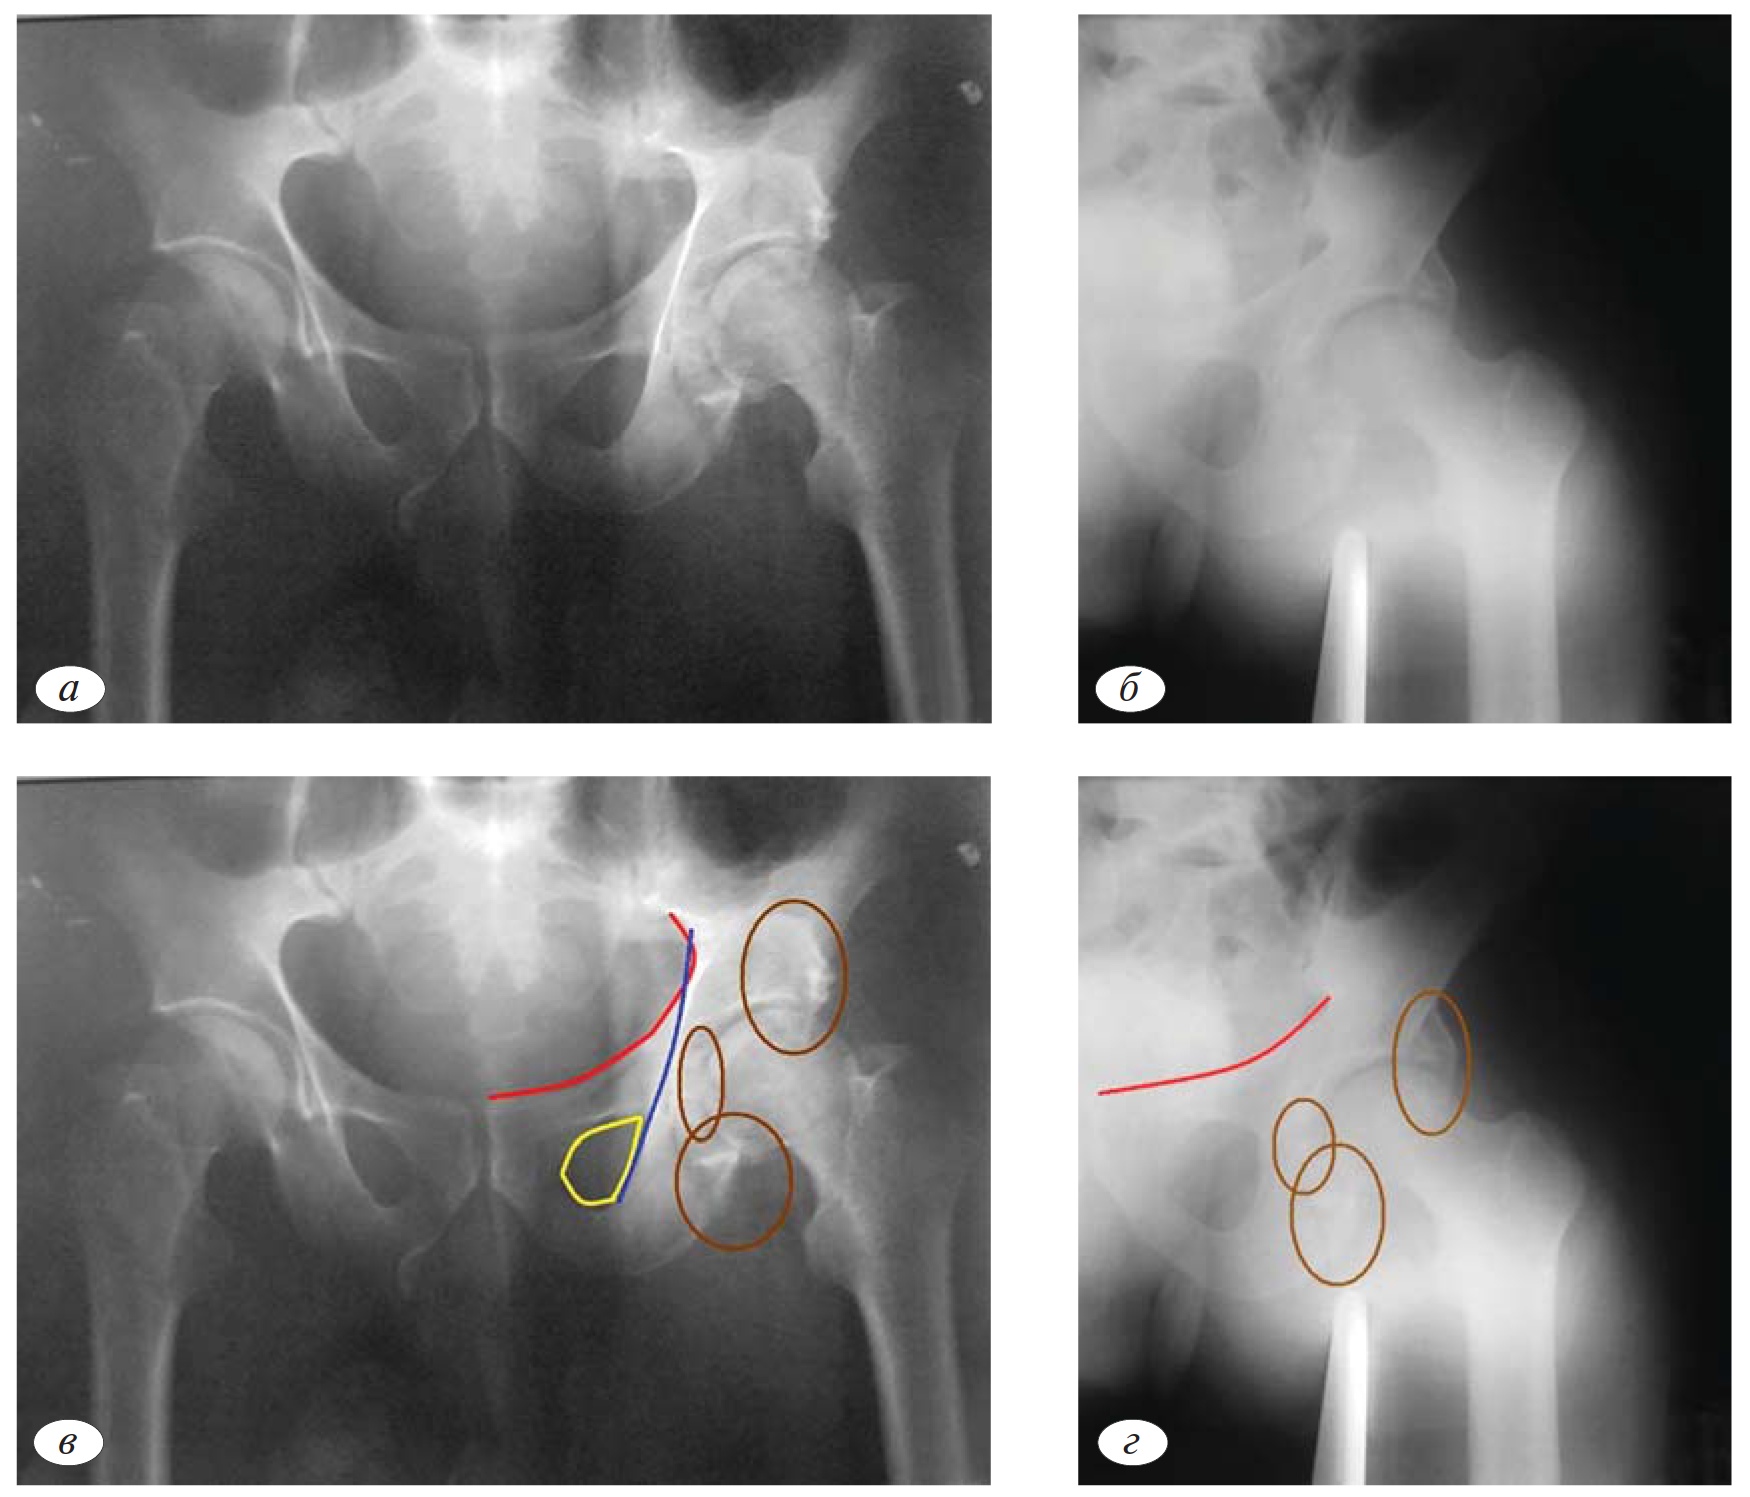

Сложность рентгенологической анатомии тазобедренного сустава значительно затрудняет выявление внутрисуставных отломков. Заподозрить наличие внутрисуставных осколков возможно при наличии теней костной плотности в проекции суставной щели как минимум в 2 проекциях (рис. 6, а—г).

Однако окончательная диагностика этого сопутствующего локального компонента повреждения возможна с помощью КТ (рис. 6д, е).

Переломы головки чаще встречаются при переломах вертлужной впадины с локализацией очага в задних отделах (задняя колонна, задняя стенка). Перелом головки довольно часто носит импрессионный характер и проявляется в виде участка вдавления верхнего полюса головки (рис. 7, а, б). Наиболее часто повреждения головки бедренной кости наблюдаются у пациентов старше 40 лет, что обусловлено снижением качества костной ткани.

В некоторых случаях импрессионных переломов головки рентгенография не является достаточно убедительной для верификации. Окончательное определение повреждения головки бедренной кости проводим по данным КТ (рис. 8, а, б). Сочетание перелома вертлужной впадины и нагружаемой части головки бедренной кости является крайне неблагоприятным прогностическим признаком.

Рис. 7. Импрессионный перелом головки в сочетании с переломом задней колонны (а, б).

Рис. 8. Импрессионный перелом головки бедренной кости по данным КТ при отсутствии признаков повреждения головки по данным рентгенографии (а, б).

Рис. 6.а—г. Наличие теней костной плотности в проекции суставной щели (внутрисуставные осколки); в, г — верификация наличия внутрисуставных осколков по данным КТ.